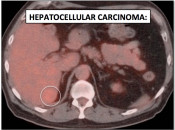

While PET/CT is sensitive for detecting most cancers, there are some malignancies which sometimes demonstrate poor avidity for 18F-FDG, including: [Fig. 1]

- Hepatocellular carcinomas

- Mucinous adenocarcinomas

- Neuroendocrine tumors

- Lobular breast cancers

- Adenocarcinoma-in-situ (formerly “bronchoalveolar carcinoma”)

- Renal cell carcinoma

- Prostate cancer

- Indolent lymphomas

Please note that while the above cancers sometimes demonstrate poor metabolic activity, they can also be quite FDG-avid. [Fig. 2]